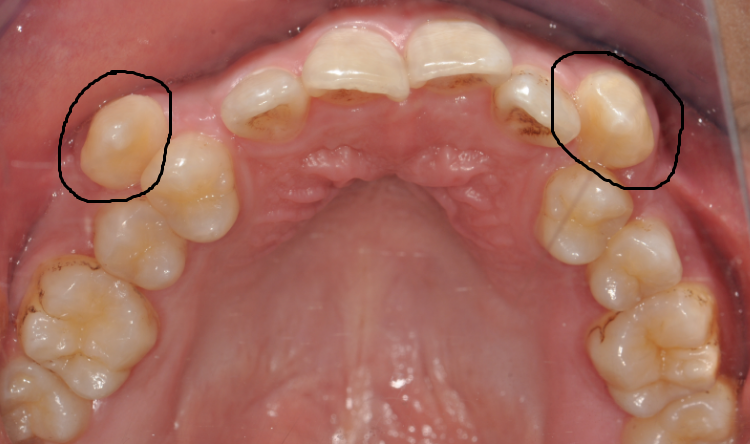

齒 嘿嘿,牙妹,我覺(jué)得我的牙齒距離就差一點(diǎn)兒了。你看我的虎牙,長(zhǎng)出來(lái)的位置不正,被擠在牙弓外面,一張嘴就會(huì)看見(jiàn),很不美觀。別的牙還挺齊的,所以我想能不能直接把虎牙拔掉,這樣就用簡(jiǎn)單的方法解決了問(wèn)題。(圖片1 2)